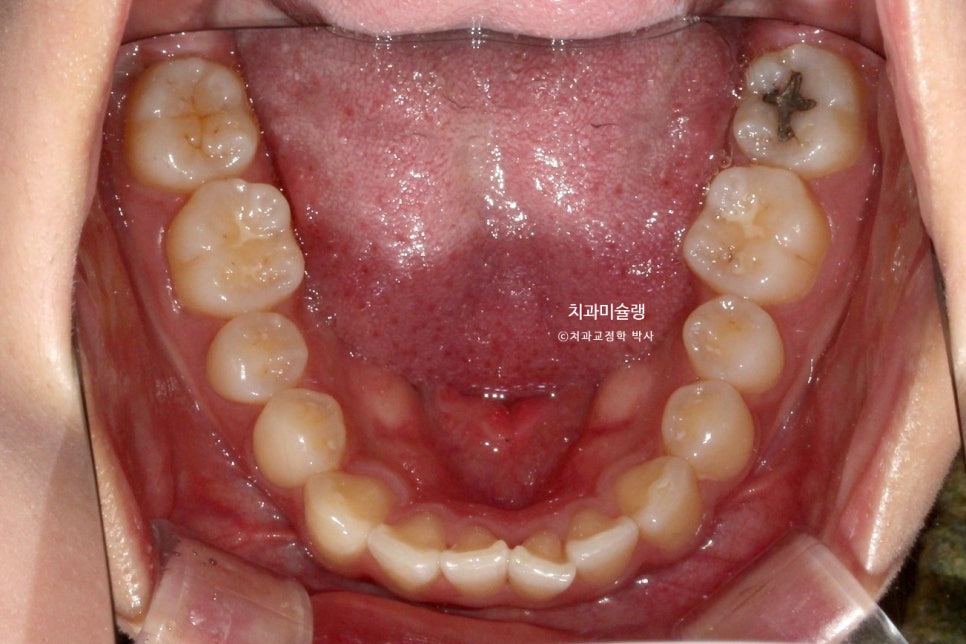

중심선 불일치, 앞니 벌어짐이 보입니다.

작은어금니를 발치할 정도의 돌출은 아니라 비발치 돌출입 교정 권유드렸습니다.

더불어 아래턱을 자가회전 시켜 하관을 짧게 만들고, 무턱처럼 보이는 턱끝도 개선하기 위해 상악 전체치열 후방이동과 동시에 함입도 하기로 합니다.